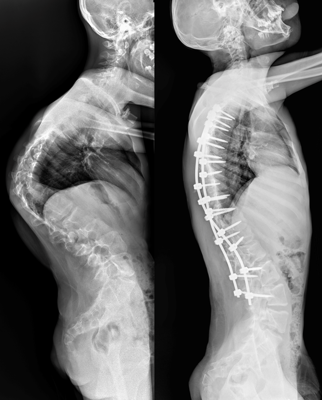

Врачи отделения травматологии и ортопедии РДКБ РНИМУ им. Н.И. Пирогова Минздрава России провели успешную операцию по коррекции кифосколиоза у пациента с синдромом Протея. Хирургическое вмешательство длилось более семи часов и было технически сложным: кифотическая деформация грудного отдела позвоночника составляла более 110 градусов, а комбинированная сколиотическая — по 90 градусов в грудном и поясничном отделах. Благодаря слаженной работе опытной команде хирургов удалось добиться существенной коррекции и обеспечить пациенту достойное качество жизни в будущем. По словам врачей, мальчик даже сможет заниматься своим любимым делом — кататься на велосипеде.

«К нам он поступил с уже существенным искривлением позвоночника. Кифотическая деформация грудного отдела составляла более 100 градусов, а сколиотическая — более 90 градусов в грудном и поясничном отделах. Отмечались нарушения походки, а совокупность этих и других проблем пациента, связанных с основным диагнозом, сильно влияла на его качество жизни», — отмечает Андрей Андреевич.

«Основой вмешательства стала стандартная методика. Дорсальным доступом мы установили транспедикулярные винты (через ножки дуг в тела позвонков), затем при помощи специальных корригирующих маневров постепенно привели деформацию в оптимальное положение и зафиксировали стержнями», — объяснил хирург.

Установленная металлоконструкция получилась достаточно протяжённой: от третьего грудного (Т3) по четвертый поясничный (L4) позвонок. Хирурги постарались сохранить подвижность двух сегментов в нижнепоясничном отделе, чтобы уменьшить степень ограниченности физических возможностей пациента в будущем.

После операции Мурат быстро активизировался и восстанавливался. Хирургам удалось добиться невероятных результатов в коррекции: угол кифотической деформации был снижен до 60 градусов (практически вдвое), а сколиотических — до 40-50 градусов, обеспечен удовлетворительный баланс позвоночника в сагиттальной и фронтальной плоскостях.